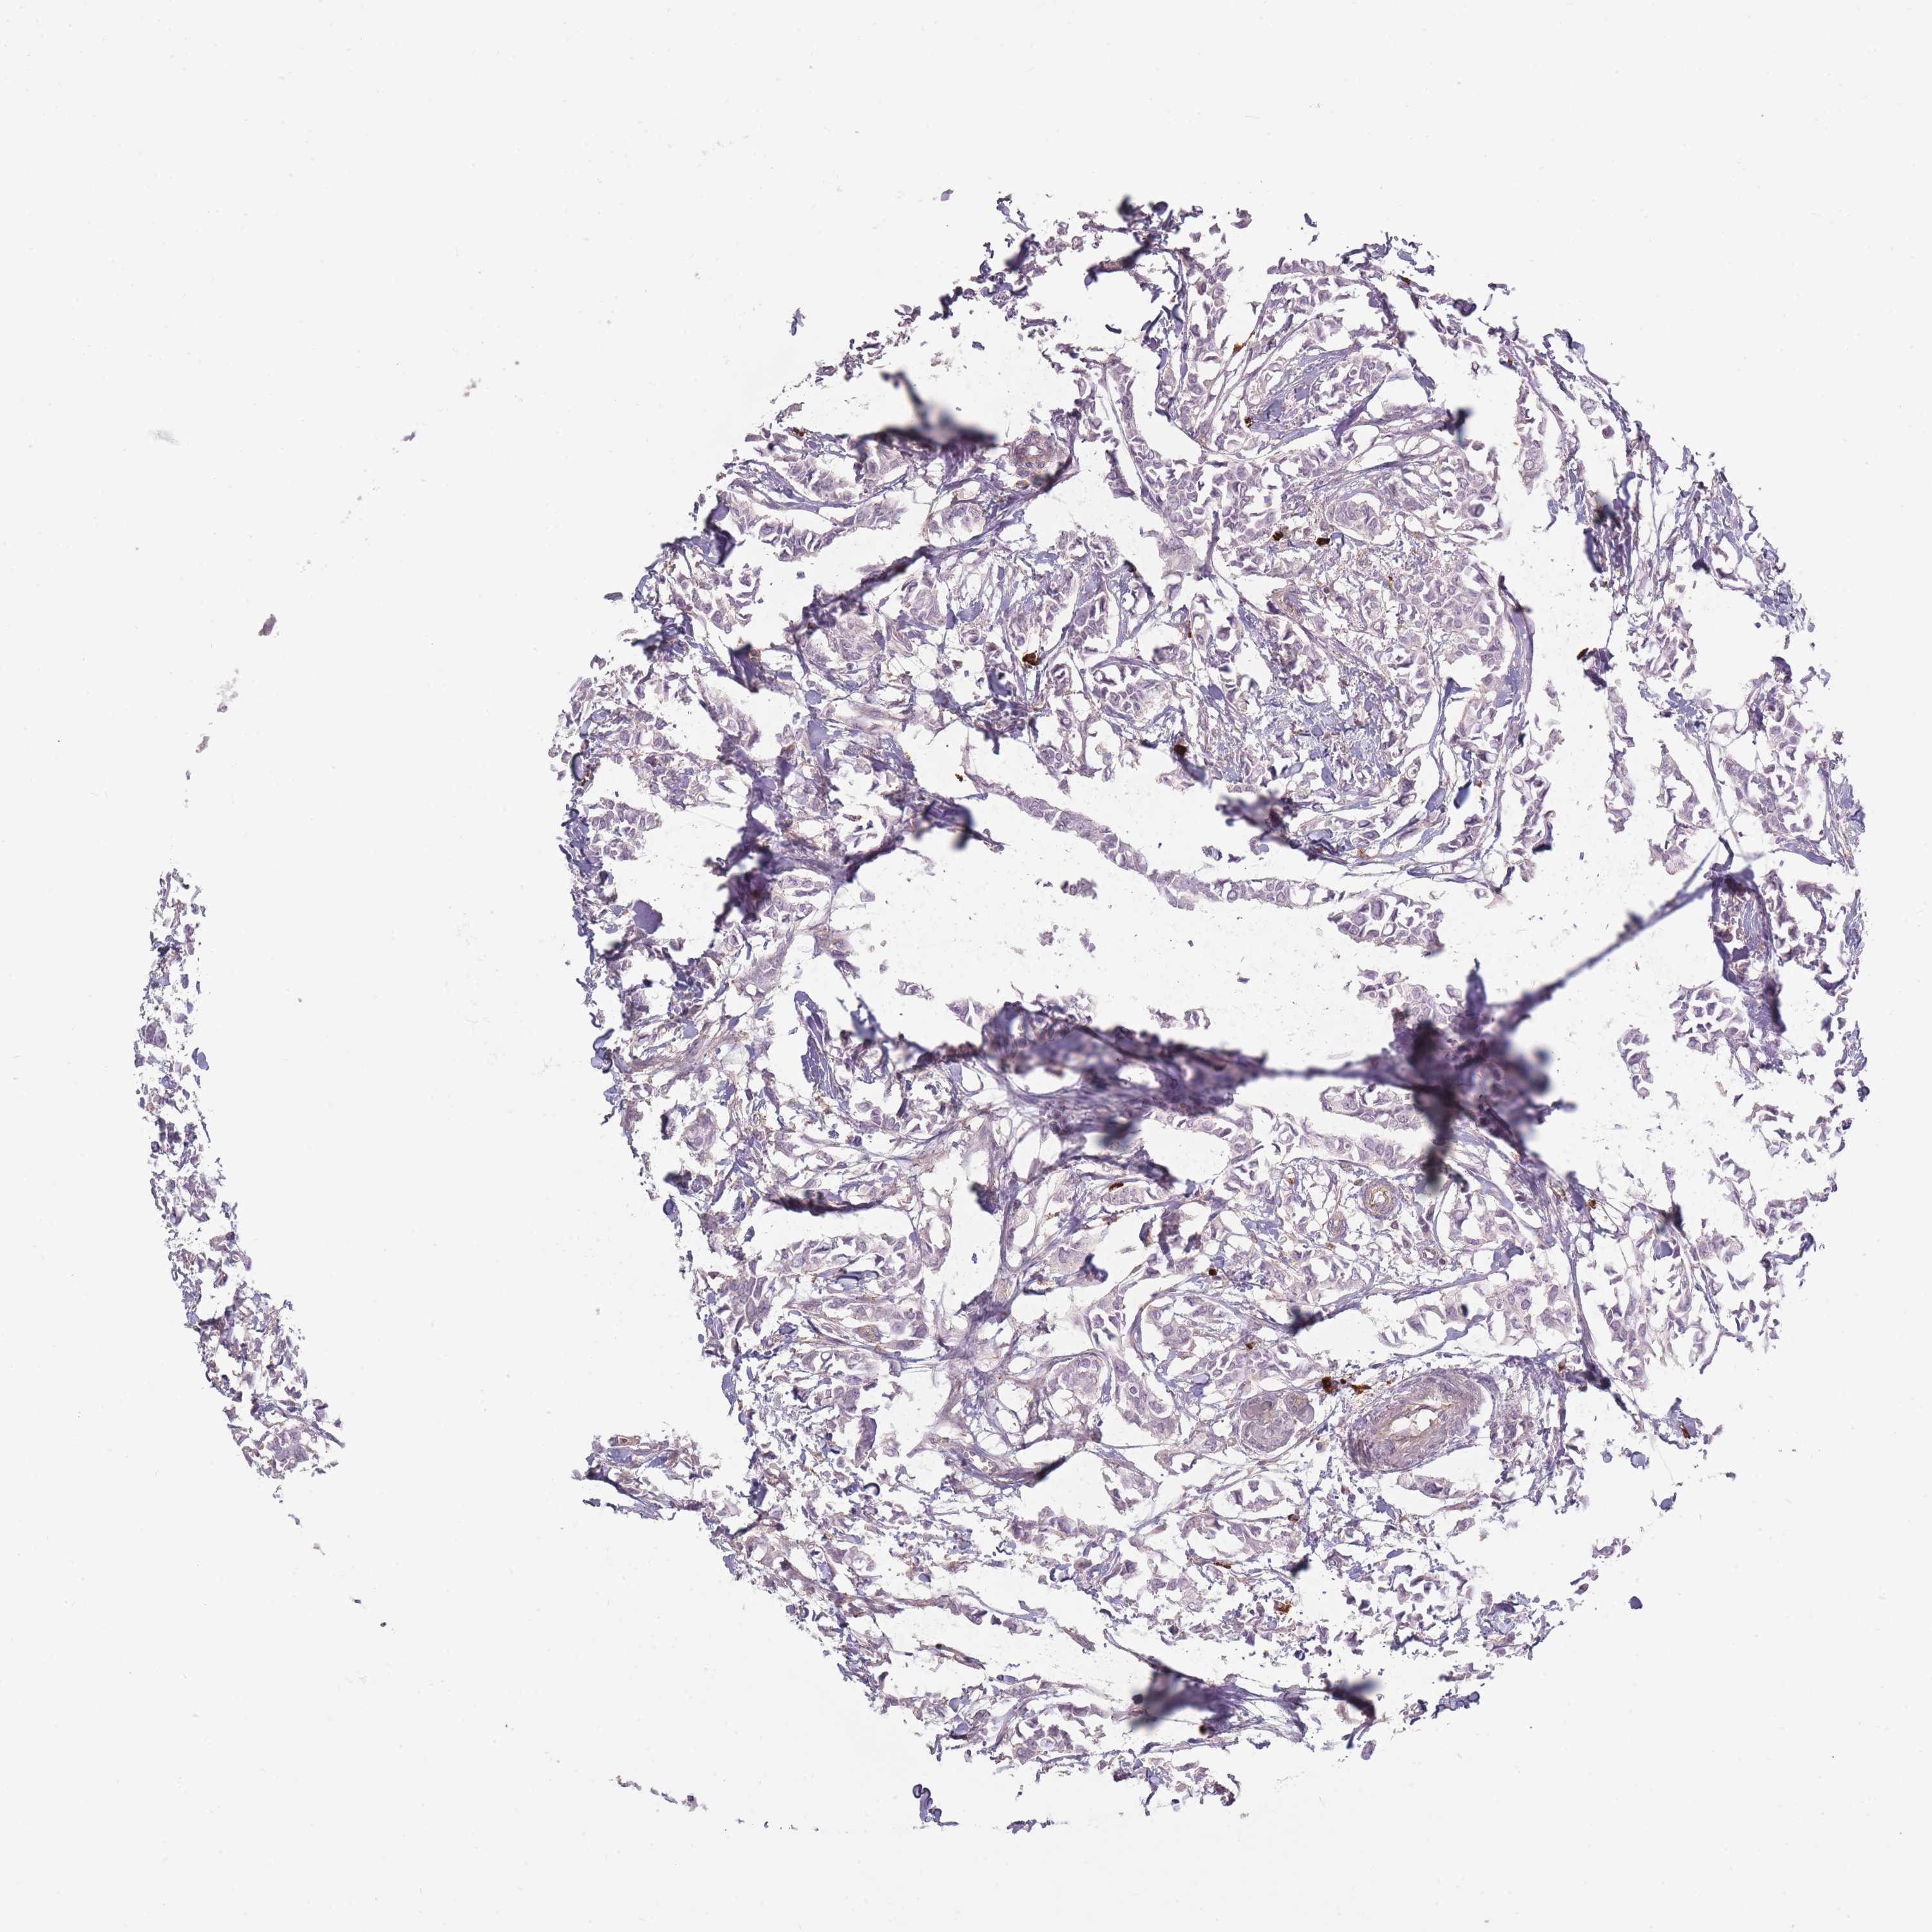

BRCA TCGA BRCA VALIDATION PROTEIN EXPRESSION

ANTIBODIES

AND

VALIDATION